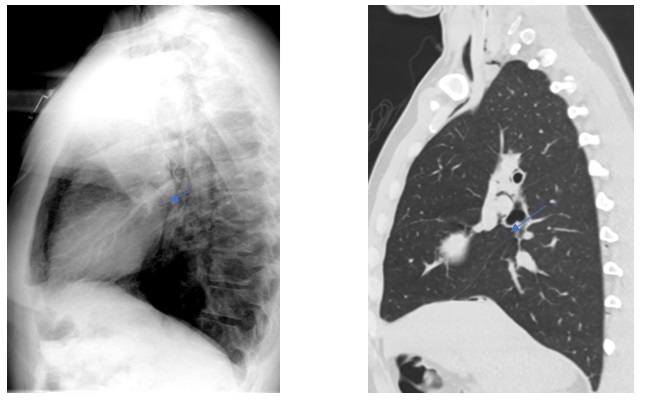

Dentro de los métodos diagnósticos, el neumomediastino se puede diagnosticar mediante radiografías o tomografía computada, donde se va a visualizar la presencia de aire (radiolucidez o hipodensidad lineales) rodeando las estructuras mediastinales. Un signo de muy alta especificidad es el llamado “signo del anillo alrededor de la arteria”, donde se visualiza una imagen radiolúcida o hipodensa en forma de anillo rodeando la arteria pulmonar, principalmente del lado derecho. Este signo ayuda a diferenciar esta entidad del neumopericardio, que puede verse similar en imágenes.

Among the diagnostic methods, pneumomediastinum can be diagnosed using X-rays or computed tomography scans, where the presence of air (linear radiolucency or hypodensity) surrounding the mediastinal structures will be visualized. A highly specific sign is the so-called “ring sign around the artery”, where a radiolucent or hypodense ring-shaped image is visualized surrounding the pulmonary artery, primarily on the right side. This sign helps differentiate this condition from pneumopericardium, which can appear similar on imaging.